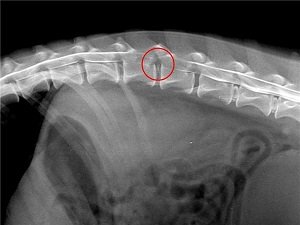

Для исключения механических повреждений позвоночника проводится рентген. Применение контраста позволит точно определить место поражения. Рентгенограмма оценивает состояние межпозвонковых промежутков. Контраст очерчивает контуры спинного мозга и нервные волокна, визуализирует их степень компрессии. Также информативными методами диагностики можно считать КТ, ИРТ. Но такие исследования проводятся не в каждой ветклинике, они более дорогостоящие, чем рентген.